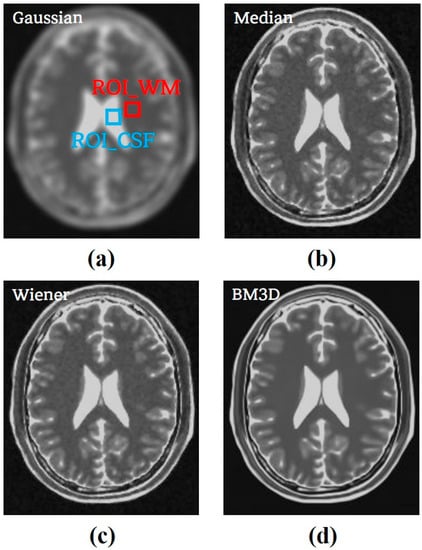

3.1. Simulation Study

3.2. Clinical Study